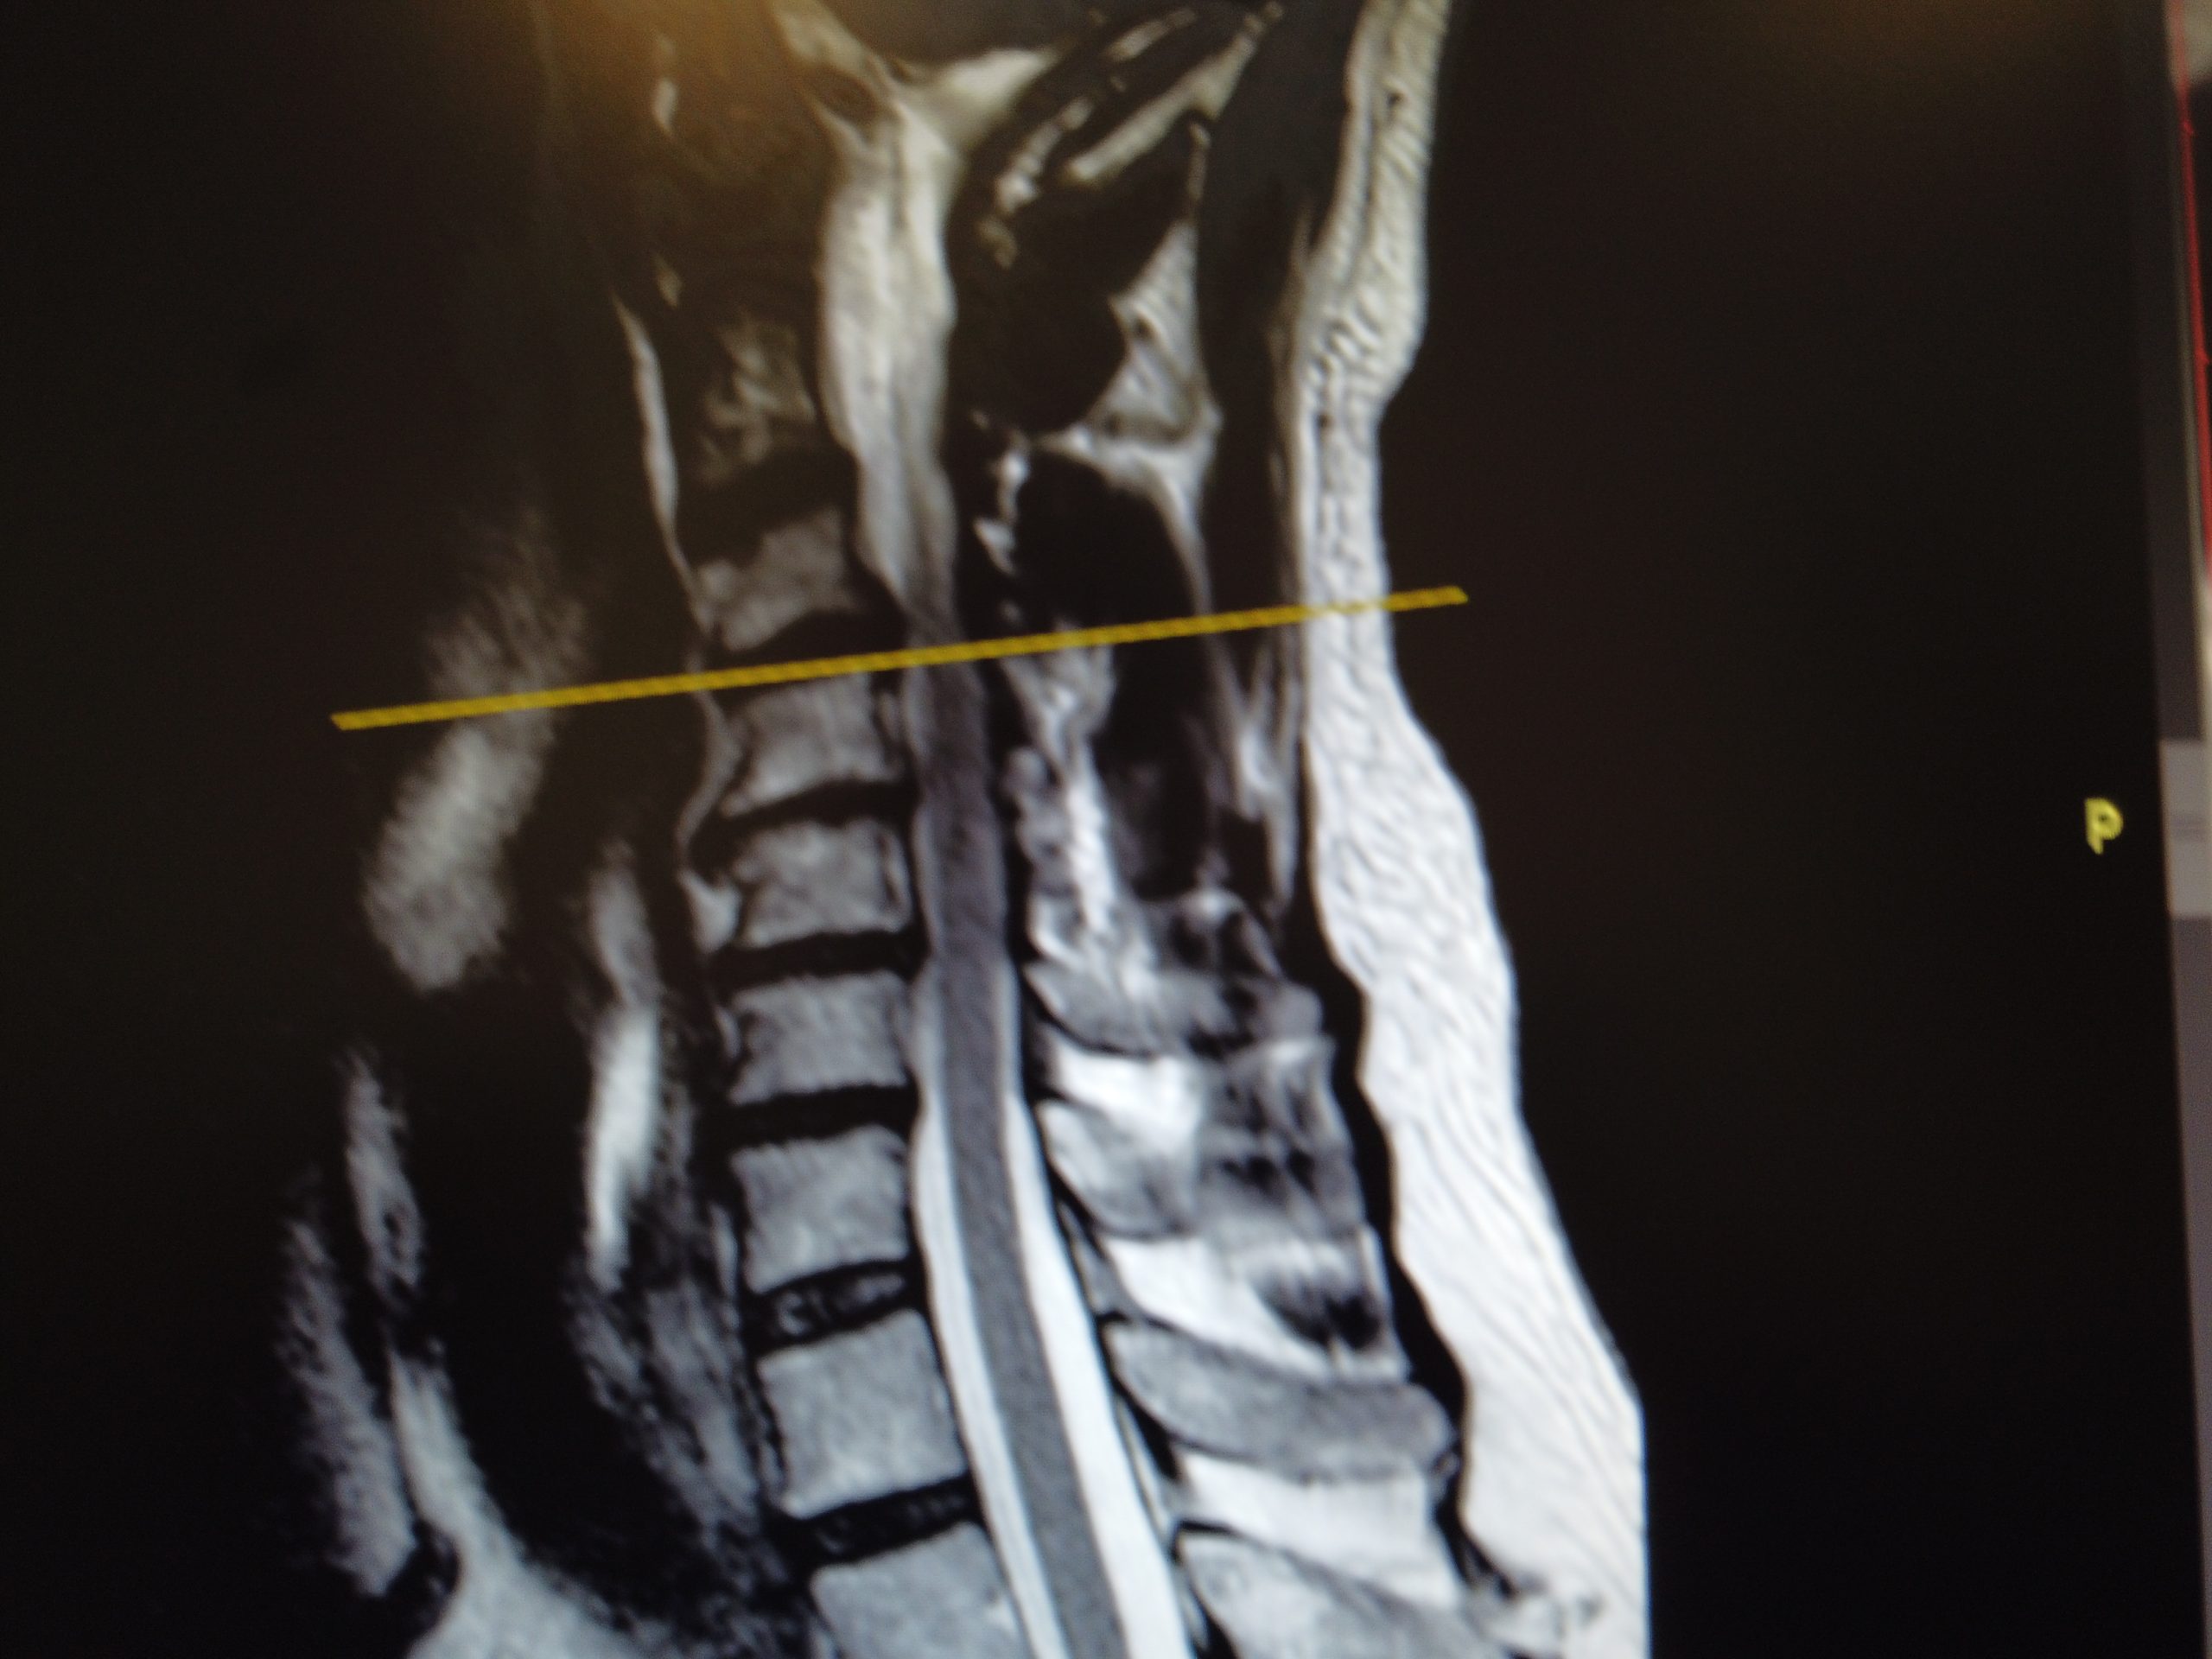

El paciente presenta varias hernias discales cervicales, con ciertas complicaciones debidas a la artrosis sufrida en la zona. Se reflejan de manera lateral

En el corte lateral se observan varias hernias:

• Una hernia de mayor tamaño entre la 3º y la 4º vertebral cervical

• Otra hernia más pequeña entre la 4º y la 5º vértebra derecha en este caso

• Una última entre la 5º y la 6º derecha, extendida hacia la izquierda

Son hernias multinivel, que se reflejan en el paciente con síntomas principalmente en el lado derecho.